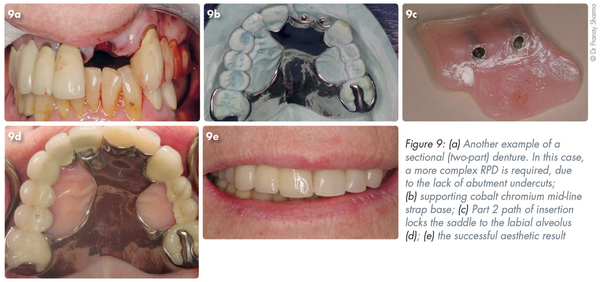

A further scenario is seen in Figure 9a. Trauma has resulted in an irregular alveolus in an otherwise complete dentition. The abutment teeth (#21, #33) are crowned and therefore the ideal fixed replacement (or implants) are unsuitable. Due to the lack of abutment undercuts a simple RPD will not provide effective retention. A cobalt chromium mid-line strap base (Part 1) provides support (Figure 9b). The path of insertion of Part 2 (Figure 9c) locks the saddle to the labial alveolus covering the defect aesthetically (Figure 9d-e).